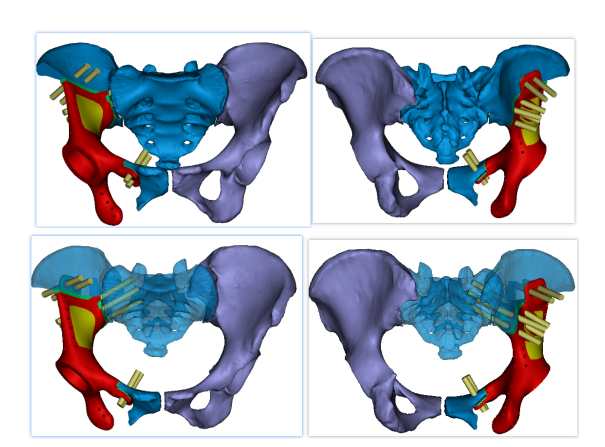

图5 三维数字模型

图6 假体及螺钉模拟效果